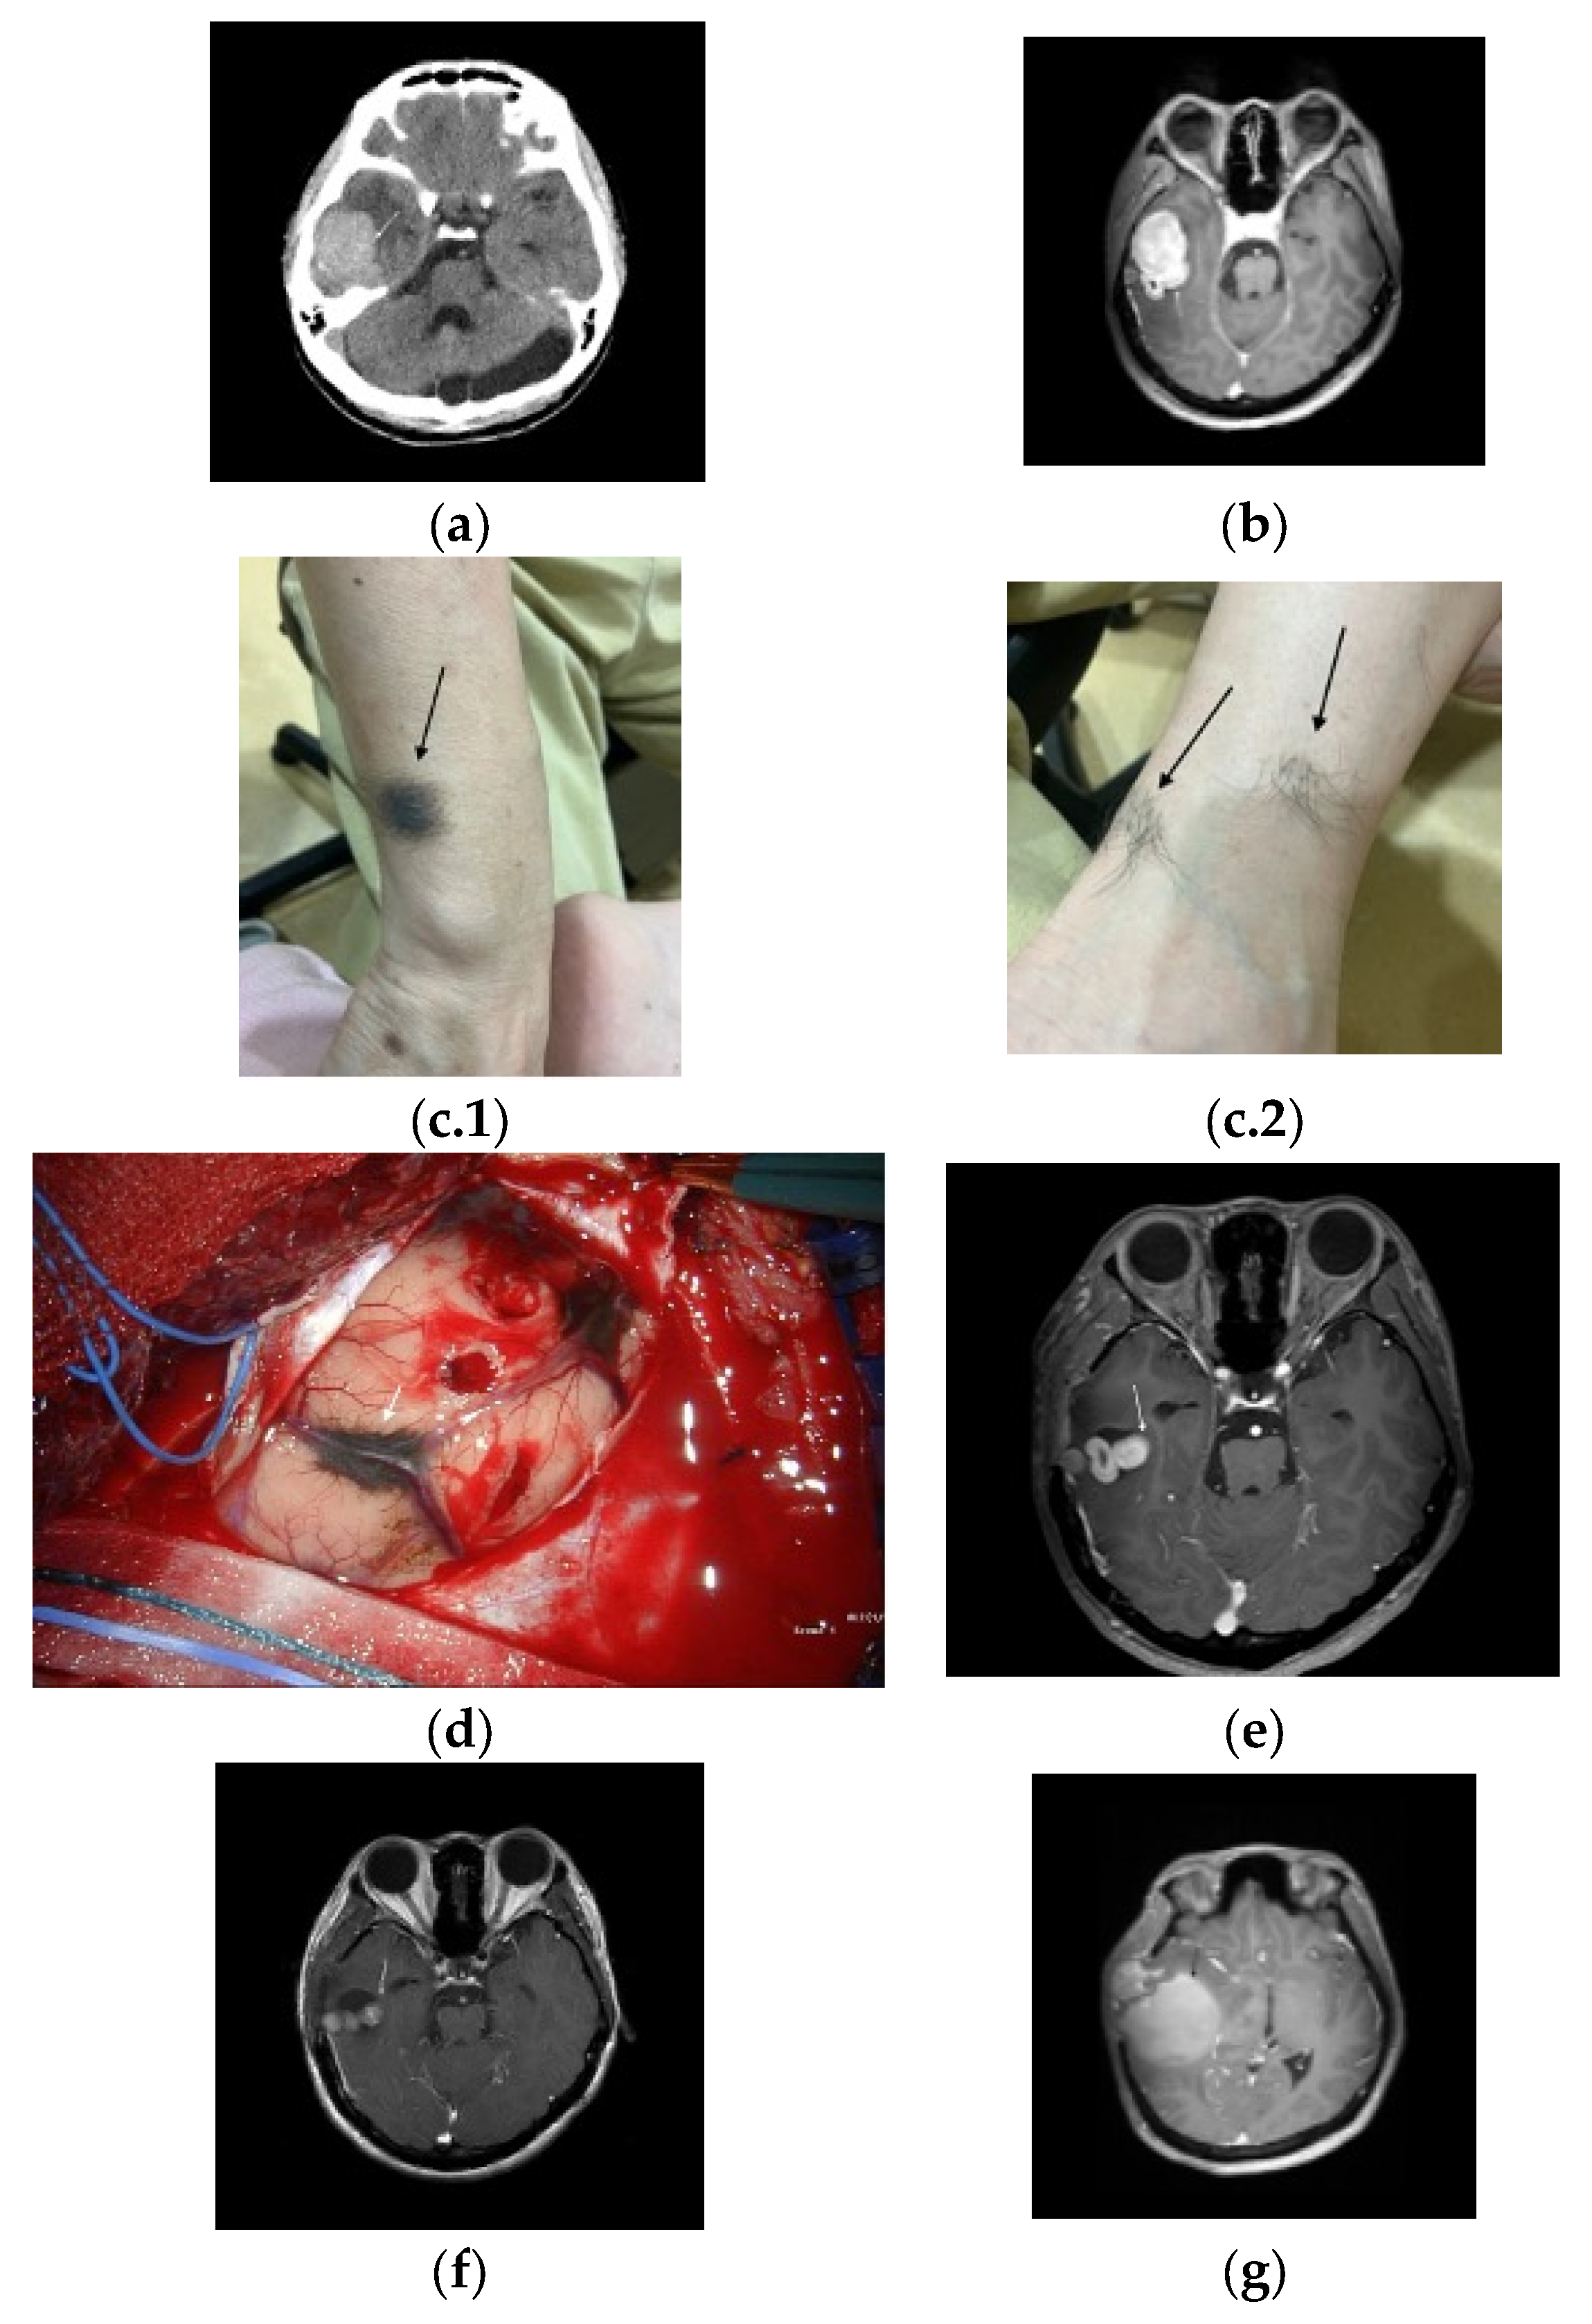

2. Detailed Case Description

| Present case | 43/ F/ Asian | Right temporal (intracranial) | Leptomeningeal (spine); bone, liver, etc. | Surgery (subtotal) + Gamma Knife; Early pembrolizumab; Ipilimumab on progression | Early (~1-month post-transformation) | Improved mobility after pembrolizumab; later decline | ~15 months after the initial diagnosis | ~15 months PT (2.5 years from initial) | 50% |